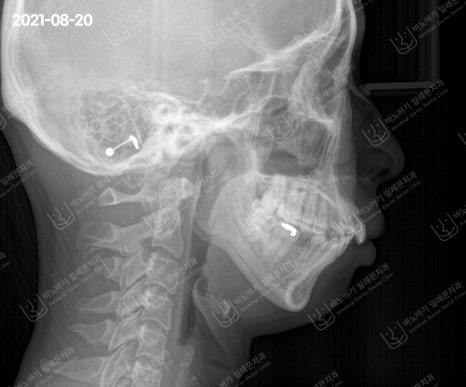

좀 더 구체적으로 살펴보고자 두경부 엑스레이를 촬영한 다음 골격 부조화를 검토하였습니다.

방사선 사진으로 보았을 때에 위턱과 아래턱 간 상하 균형이 적절한 수준으로 관찰됐습니다.

턱뼈의 크기도 이상이 없으며, 무턱 양상도 잘 안 보였습니다. 다만 앞니가 약간 깊게 물린 과개교합으로 확인되었습니다.